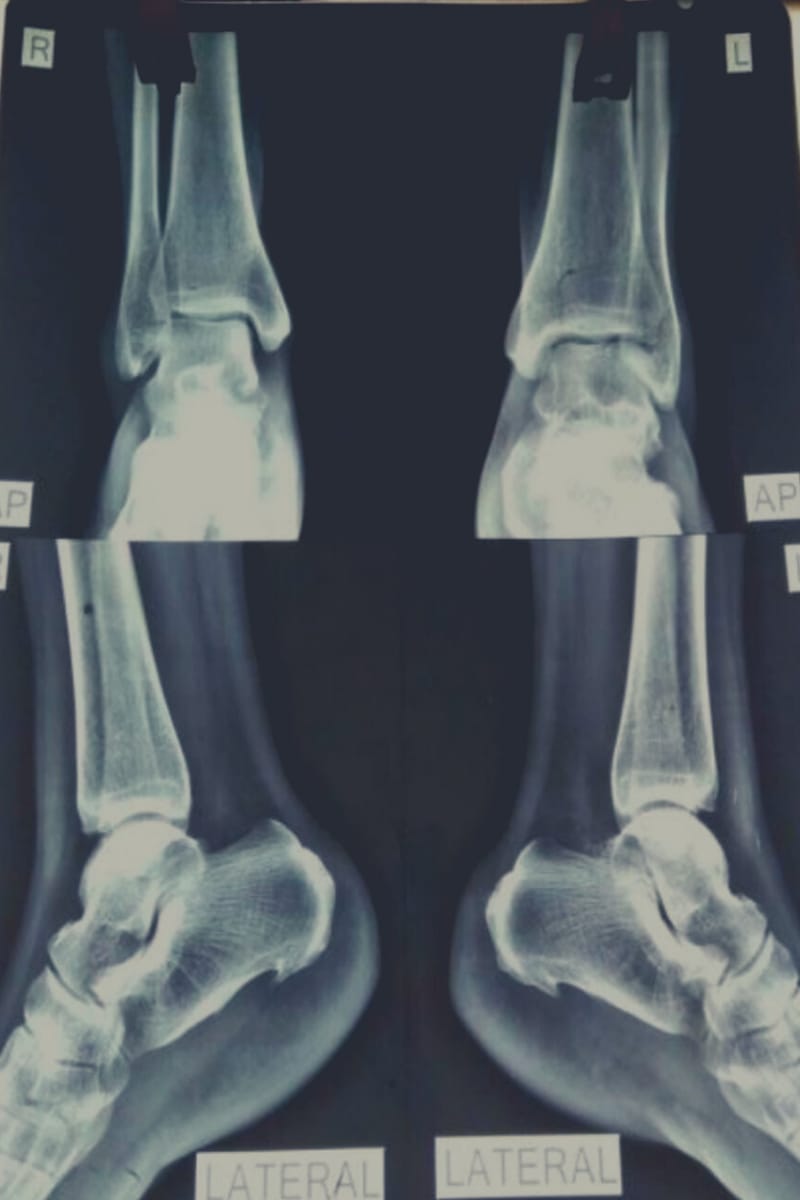

Mrs.S.M a domestic help consulted me for her heel pain, skiagram shows bilateral calcaneum spur which is so troublesome that she cannot discharge her duties properly. She has consulted two of my colleagues previously both quality prescribers on consulting their prescriptions I found that while one have prescribed on the basis of pathology in consideration of local modalities, the other have prescribed the constitutional remedy, taking in account the generalities meanwhile she also consulted an orthopedic surgeon who have advised her conservative management and painkillers, the utter failure of both of my esteemed colleagues led me to take the case in detail, giving emphasis on past history and the family history only to find few cases of suicide and insanity in numbers of close relatives. This was a clear indication of syphilitic dyscrasia in background. Considering this background and bilateral symmetrical pathology I prescribed Syphillinum 200 with a marked relief of the symptom in next follow-up after two weeks patient continued on placebo for next two months with almost total disappearance of the troublesome pain, she was asked to report with a skiagram of both the feet in vain as she never showed-up afterwards and was presumed to be relieved of her complain and discharging her duties as domestic help properly.